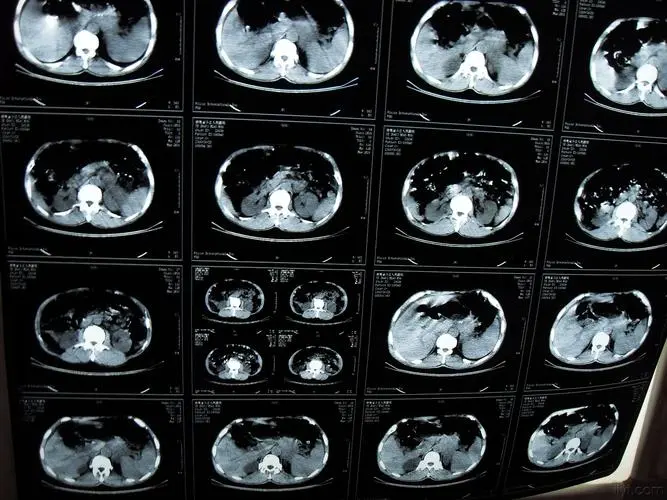

如果是这一些长期胃病的病人 , 出现了不愿意吃饭 , 或者是胃口下降 , 短期内比较迅速的消瘦的情况 , 千万不能掉以轻心 , 要到医院里面进行进一步检查 , 比如说是胃镜检查 , 如果发现有可疑的病变 , 要进行病理活检 , 如果发现是胃癌 , 就要马上进一步的处理 。